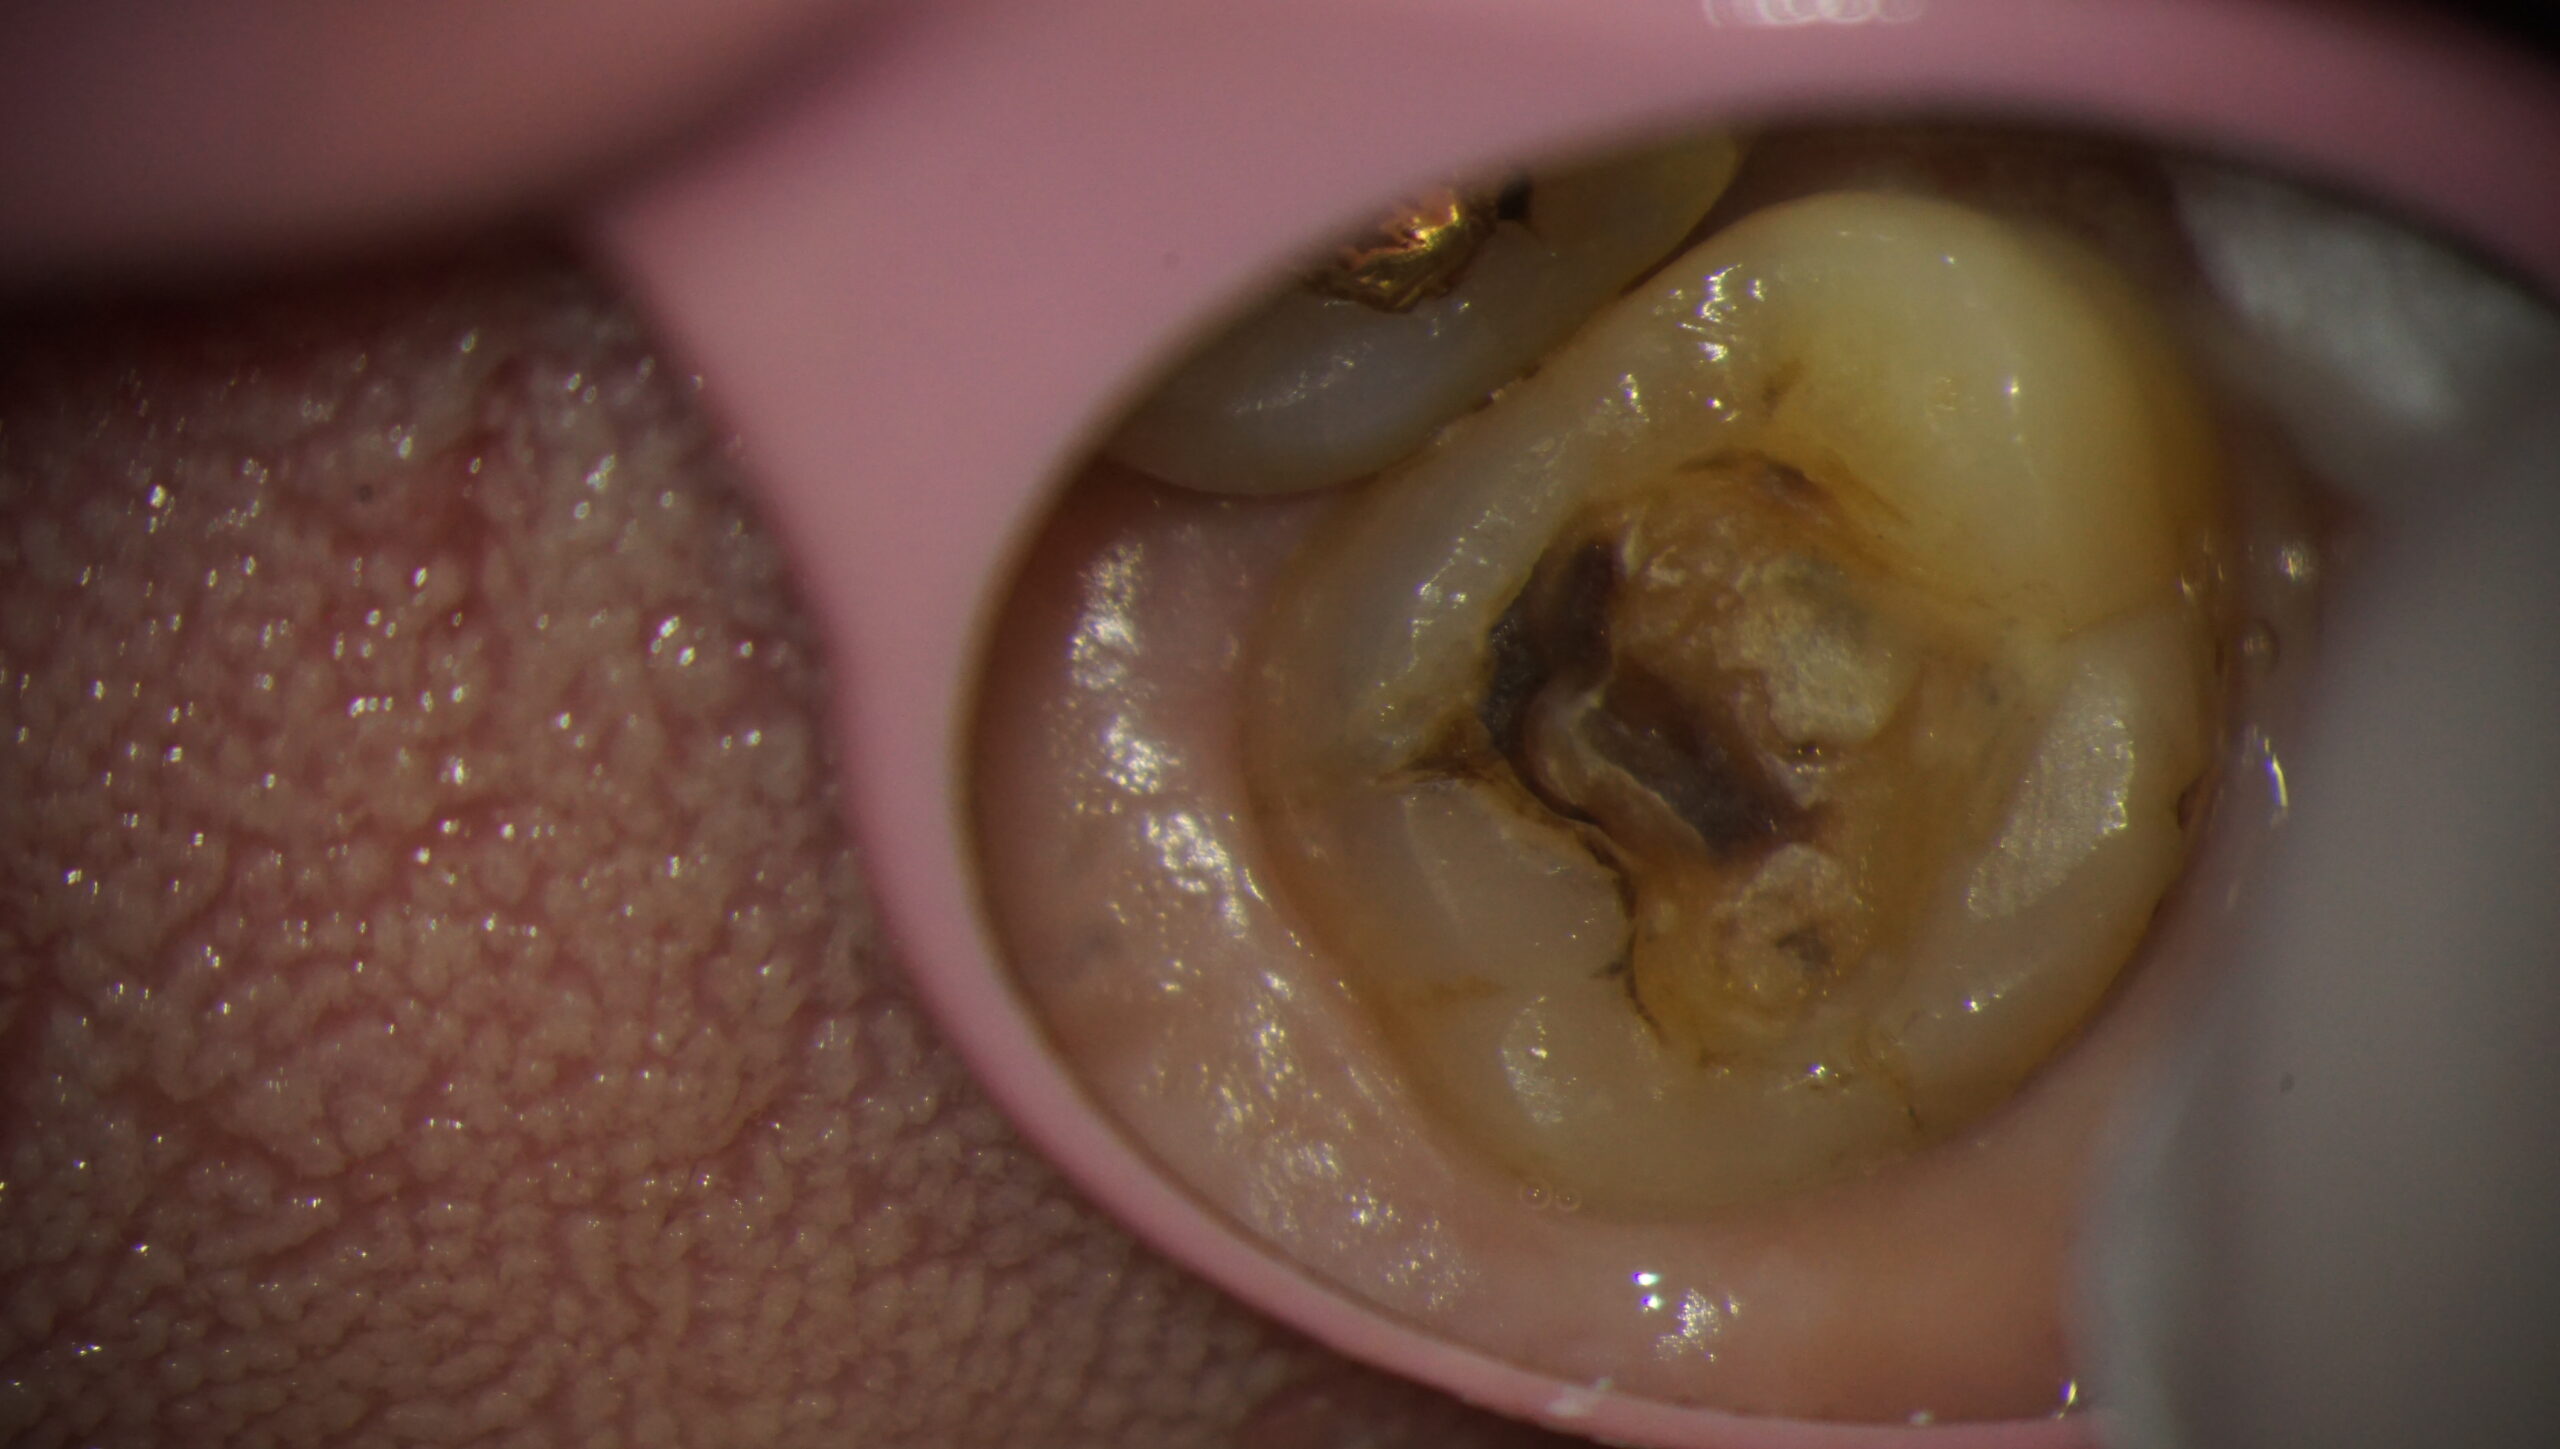

入っていた金属が外れてやり直すことになった患者さんです。

中が黒くなっており、虫歯であることがわかります。

金属の修復が劣化し、中に虫歯が入ったということも想像されます。

別の方向から歯を見てみましょう。

歯の真ん中に大きなヒビが入っているのがお分かりいただけますでしょうか。

ちょうどこの部分です。

マイクロクラックは、歯に入るヒビ割れのことを言います。

我々人間にとってはただのヒビですが、虫歯菌にとってはとても大きな隙間です。

歯の内部に簡単に侵入することができます。

そして中で虫歯を作るのです。